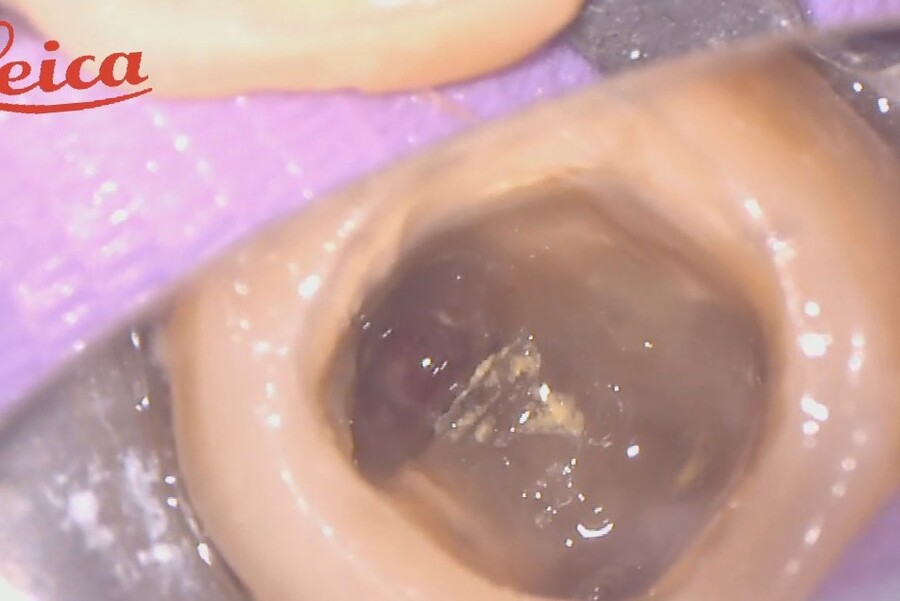

根管充填直前

はじめは根の中に開いた穴から出血していますが、精密根管治療によって出血は止まり、根管充填直前ではかさぶたができています。